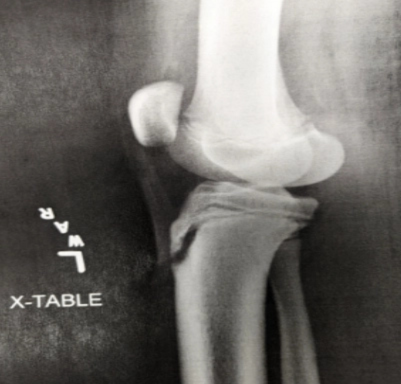

A 12 yo boy presents to the ED with anterior left knee pain. He has been having pain on-and-off for several weeks, beginning when he started playing basketball for his school team. Yesterday, the pain was worse, and he had to sit out of a game, which his father states is unusual for him. He denies any specific injury, and he denies any “pops” or feeling of instability in the knee. He took ibuprofen prior to arrival, and this helped alleviate some of the pain. He has not tried any other treatment modalities. On exam, he has point tenderness on the proximal anterior tibia in the midline of the lower leg. He has no edema of the knee itself, and the knee is grossly stable. He has no pain with internal and external rotation of the hip. He ambulates normally but states it will hurt to run or jump. The following radiograph is obtained.

Image by exclusive permission of personal collection of Ashley Barrile, M.D. All rights reserved